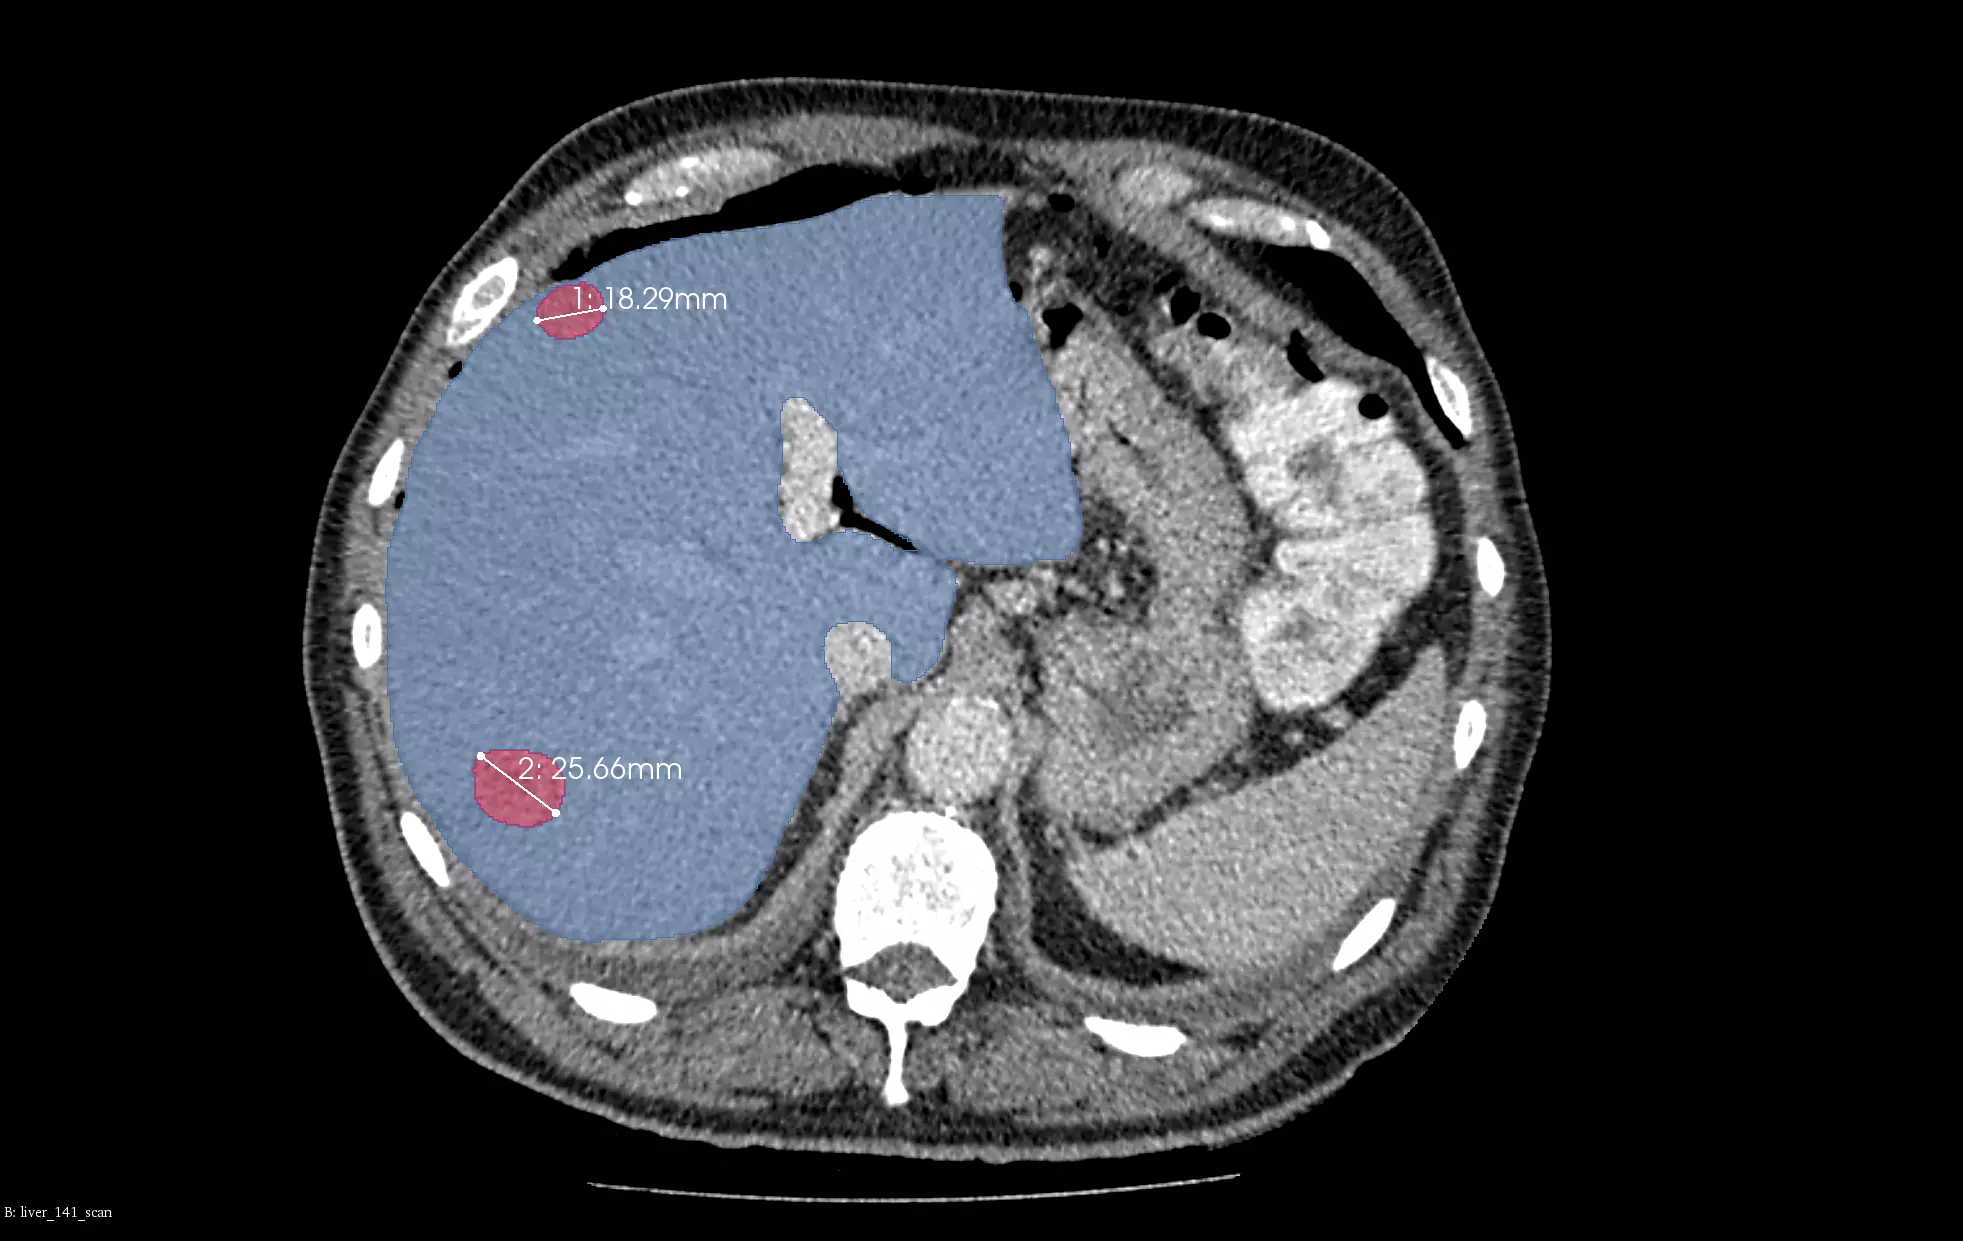

In the above example, we present our models for liver and liver tumor segmentation. The image shows primary tumors, secondary tumors and metastases. It is based on portal venous CT scans. For clarity, only the two biggest lesions are marked in the visualizations.